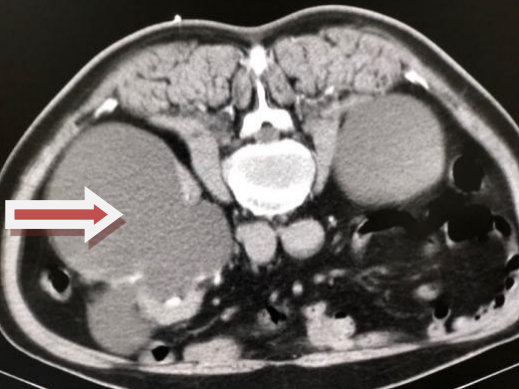

入院后,在做完相應(yīng)的術(shù)前準備后,患者接受了介入治療。此次手術(shù)是在CT引導(dǎo)下進行的,經(jīng)皮腎囊腫穿剌抽吸硬化介入治療。躺在CT檢查床上,可以看出患者還是有些緊張的。

囊腫已明顯縮小,最終會完全消失